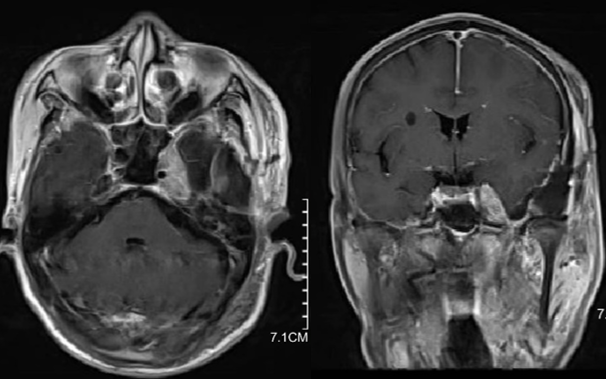

患者,男,72岁。2023年7月因“左面部麻木1月余”检查发现左侧海绵窦肿瘤并向后颅窝生长(图1),当时其他医师手术切除了后颅窝小部分肿瘤(图2),术后病理:脑膜瘤,WHO I级。

术后患者接受了伽马刀治疗。患者左眼视力明显下降。2024年3月因头部外伤复查,MRI检查提示右侧硬膜下血肿,左侧海绵窦肿瘤明显增大(图3)。当时予以阿托伐他汀保守治疗。